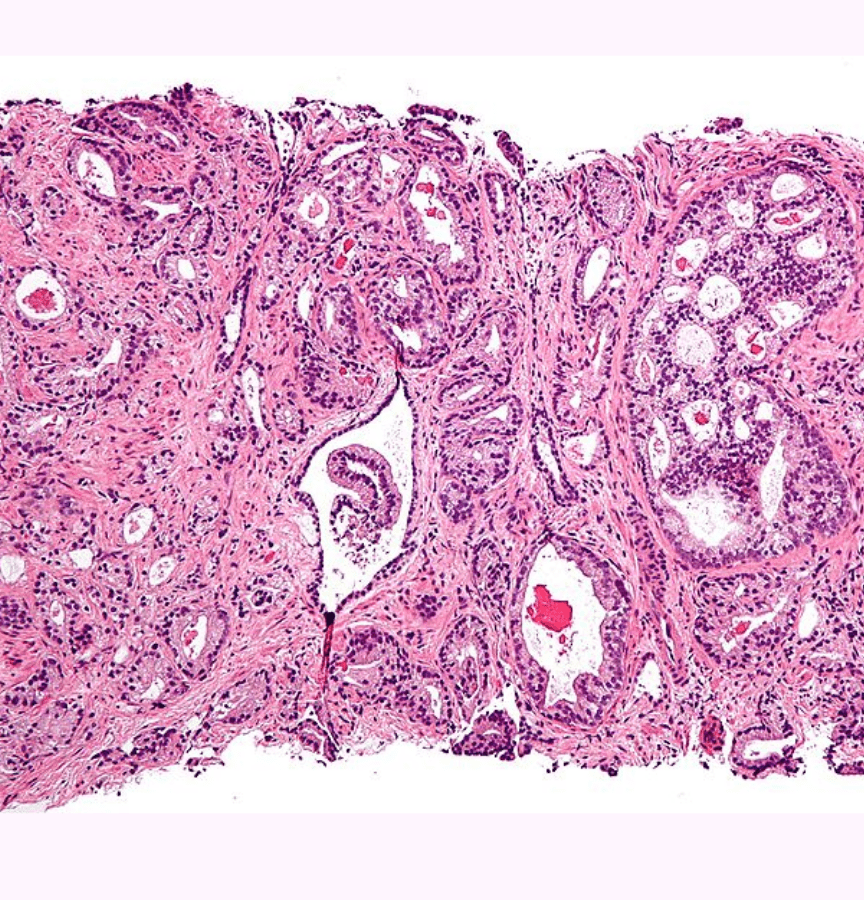

Metastatik prostat kanseri, bilgisayarlı tomografi ve kemik taramalarında görülebilen prostattan vücudun diğer bölgelerine yayılmış bir kanser türü. Metastatik hormona duyarlı olan prostat kanseri hastaları için standart tedaviye enzalutamid hormonu içeren bir androjen reseptör blokerinin eklenmesi yüzde 67’lik bir hayatta kalma oranı sağladı.